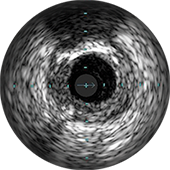

Цифровой катетер для ВСУЗИ Eagle Eye Platinum

ВСУЗИ